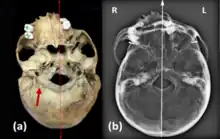

Um esqueleto de um individuo com cerca de 25 anos que foi um soldado do exército real jugoslavo, apresenta fusão do atlas e do áxis o que causava limitação na rotação do pescoço, identificada como síndrome de Klippel-Feil tipo II (Leggio e colaboradores, 2022)[10]. Na análise craniana verificou-se uma assimetria do parietal e occipital causando deformação no crânio, observou-se também uma hipoplasia condilar occipital bilateral e assimétrica do foramen magnum (figura 4), onde se verifica que, embora os côndilos estejam completos estes são assimétricos e deve-se à fusão das vértebras anteriormente referidas. Há também um desvio no septo nasal (figura 4), mas pode ter ocorrido devido a outros fatores que não a síndrome. Analisando a coluna vertebral, verificou-se que este individuo tinha escoliose e spina bifida occulta, sendo estes sintomas da síndrome de Klippel-Feil (tal com citado em Leggio et al, 2022)[10].